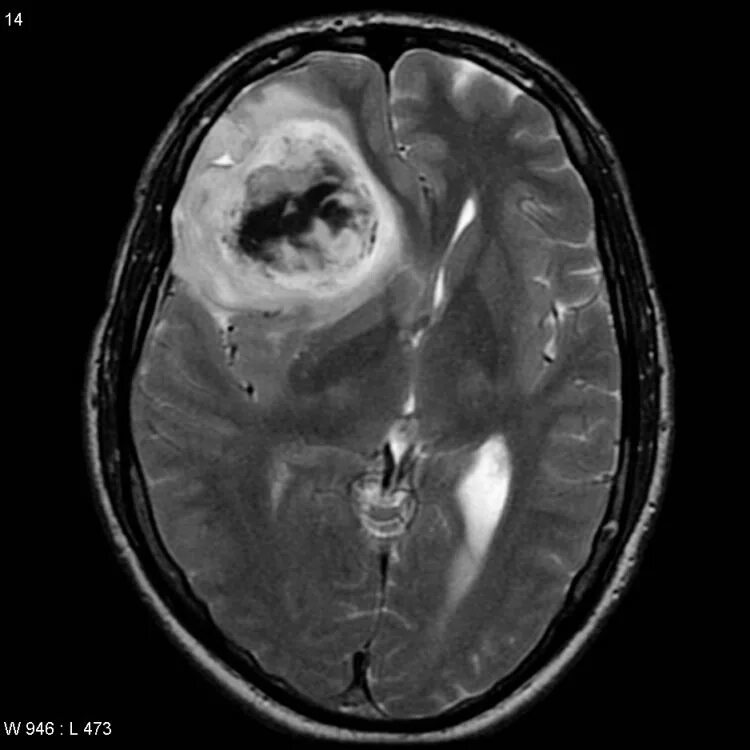

Как выглядит опухоль на снимках